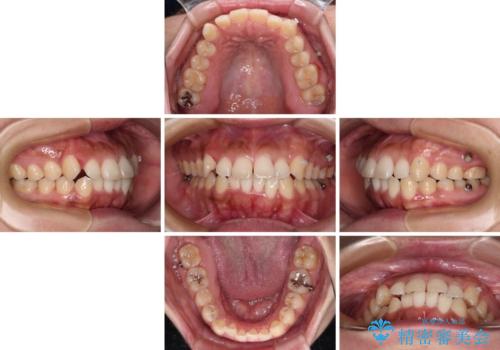

【モニター】カリエール・ディスタライザーを併用した八重歯のインビザライン矯正

- 前歯の叢生と八重歯を気にして来院された患者様です。

目立たない装置を希望とのことで、インビザラインにて矯正治療を行うこととしました。

インビザライン単体で改善することも可能ですが、八重歯とその後方にある歯列を確実移動させないと、上下正中がずれてしまう可能性があります。

インビザライン単体での治療ではなく、カリエール・ディスタライザーという補助装置を併用して、より確実性を上げることとしました。

補助装置で八重歯を解消しながら、並行してインビザラインで歯列を整えることとしました。

カリエールディスタライザーを併用したことで、すっきりとした口元になり、上下の正中を合わせることができました。